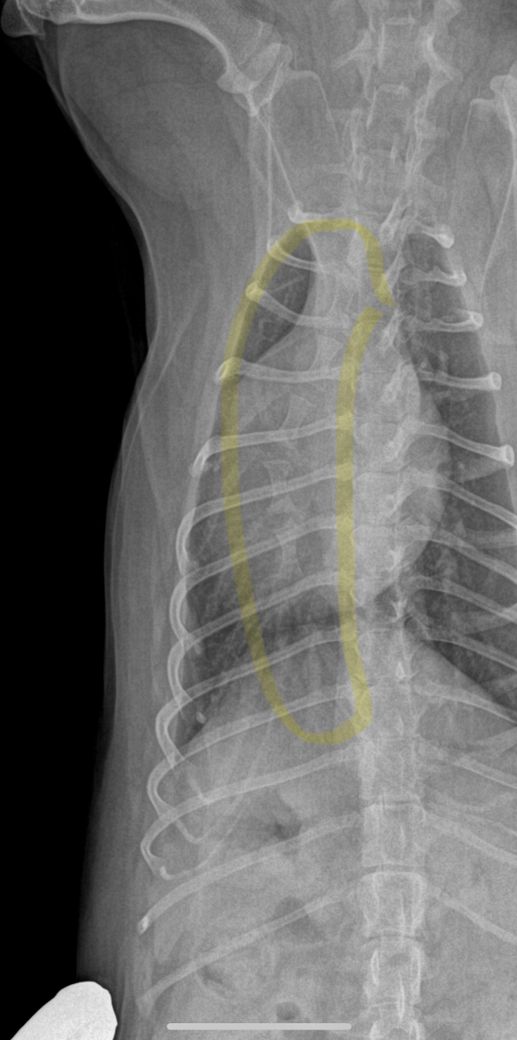

이은수 수의사님. 강아지 흉골 관련해서 답주셨는데 이 사진처럼 흉골이 휘게나왔는데 이게 촬영상이 돌아가면서 휘어보인다는 말씀이실까요? 촬영상이 돌아가면서 휘어보인다는 내용이 이해가 안가서요. 옆부분 엑스레이상 오목가슴은 아닙니다.ㅠㅠ

위 사진에서 흉골이 아니라 척추뼈를 보면 척추의 수직인 극돌기가 사진의 오른쪽으로 치우쳐 보이는 상태입니다. 즉, 환자가 촬영을 할때 사진의 왼쪽으로 돌아가서 촬영되었다는 말이지요.

아래 사진에서 흉골은 척추뼈와 일정 각도를 가지고 벌여져 있기에 촬영상에서 자세가 돌아가게 되면 마치 휘어 있는것처럼 영상이 나오게 됩니다. 이건 공간지각적으로 당연한 결과이나, 상당히 경력이 있는 수의사들도 간혹 이해하지 못하는 부분이니 보호자분이 이해가 가지 않는것은 어떤 의미에서 당연한것입니다.

결론은 정상입니다.